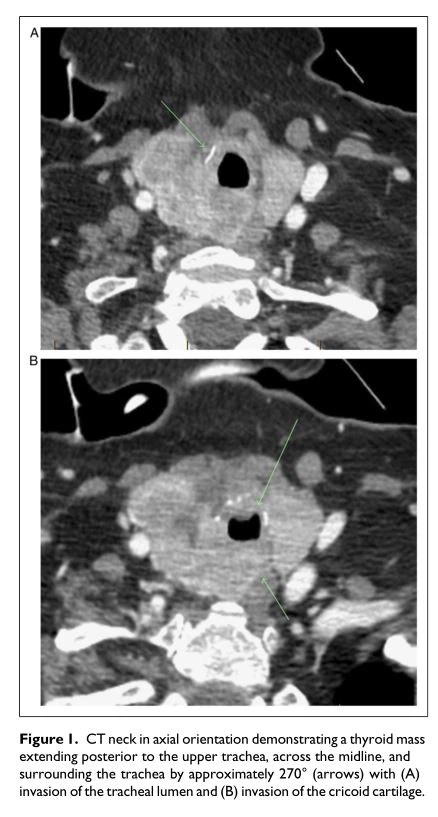

En el examen, el paciente tenía una masa tiroidea firme en el lado derecho que causaba una desviación de la tráquea hacia la izquierda. En la ecografía, apareció hiperecoico/isoecoico y mal definido, aparentemente fusionándose con el parénquima circundante heterogéneo. Nuestro equipo intentó lograr un diagnóstico de tejido; sin embargo, los intentos de biopsia por aspiración con aguja fina guiada por ecografía (BAAF) produjeron Bethesda I (x3) y Bethesda III (x2). Si bien discutimos una biopsia con aguja gruesa con nuestros radiólogos intervencionistas, optaron por repetir un FNAB ya que la tiroides parecía significativamente vascular. Durante las reuniones interdisciplinarias, decidimos realizar una biopsia en cuña de la masa tiroidea con fines de diagnóstico, seguida de una traqueotomía abierta debido a su importante traqueomalacia y sin un plazo previsible para la extubación. Se solicitó una TC de cuello y tórax de seguimiento antes de la cirugía, que demostró que la masa ahora se extendía a la superficie posterior de la tráquea superior, cruzaba la línea media y rodeaba la tráquea en aproximadamente 270 grados (Figura 1). Había invasión de la luz traqueal con la masa rodeando el tubo endotraqueal y preocupación por la invasión cartilaginosa a nivel del cartílago cricoides derecho. Además, había múltiples nódulos pulmonares pequeños bilaterales, que previamente estaban oscurecidos por focos de consolidación y preocupantes por las metástasis. Una tomografía por emisión de positrones (PET) mostró que la masa tiroidea era significativamente hipermetabólica (SUV=5.1), mientras que los nódulos pulmonares solo tenían una captación inespecífica de bajo grado (SUV=3.8). El principal diagnóstico diferencial fue el cáncer tiroideo anaplásico (ATC) dada la rápida progresión, invasividad y comportamiento agresivo de esta masa.